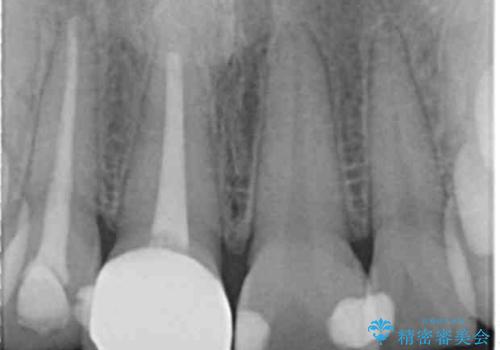

- 前歯が徐々に神経の治療を行ってから変色し、審美性の回復を求めて来院されました。

根尖に病変は見られず、根管治療は行わずに仮歯・ジルコニアクラウンを作製、装着することで審美性を回復しました。